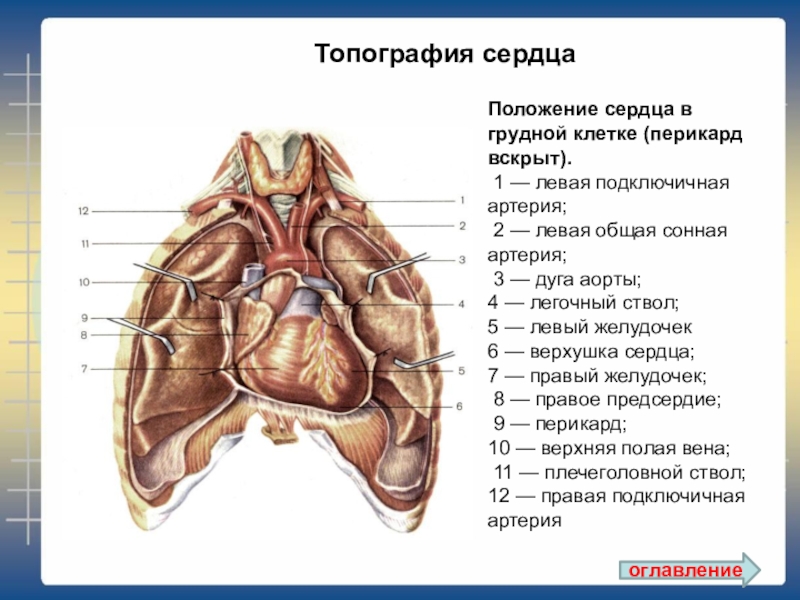

Анатомия Сердца: Расположение и Функции